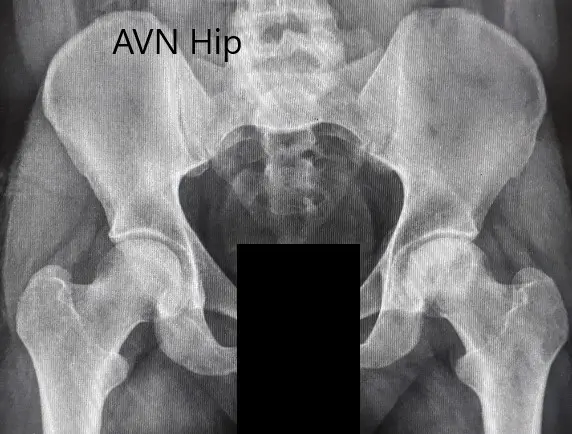

Imaging studies obtained in the form of an X-Ray suggested sclerosis of the left head of the femur. There were marked acetabulum changes. An MRI was further obtained suggesting avascular necrosis of the superior lateral head of the femur with changes in the acetabulum. There was marked hypointense areas on both T1WI and T2WIs.

Preoperative X-ray of the pelvis with both hips in anteroposterior view showing AVN of the Left Hip

Preoperative X-ray of the pelvis with both hips in anteroposterior view showing AVN of the Left Hip.